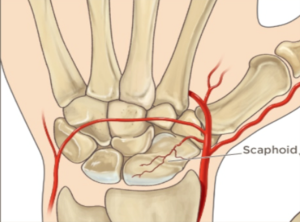

شکستگی استخوان اسکافوئید ( Scaphoid ) رایج ترین شکستگی استخوان های مچ است و تشخیص و درمان شکستگی های مچ اغلب دشوار است. این شکستگی در افراد بزرگسال جوان در اثر افتادن با دستان باز ( Falling On Outstretched Hand ) اتفاق میفتد( شکل ۱ ) . این شکستگی ممکن است که نادیده گرفته شود و فرد آن را بعنوان کشیدگی تاندون در نظر بگیرد یا ممکن است در اوایل در عکس رادیولوژی ساده قابل مشاهده نباشد . این شکستگی ممکن است دچار جوش نخوردگی شود یا اینکه بد جوش بخورد که که حرکات دست را دستخوش تغییر میکند و میتواند باعث درد و کاهش دامنه حرکتی و قدرت و آرتروز زودهنگام مچ دست شود . بهبودی، اغلب آهسته است و در بعضی موارد ممکن است جوش نخورد. برای احتیاط، در مراحل اولیه ، دست در گچ قرار میگیرد و دوباره بعد از چند هفته عکس رادیولوژی ساده میگیرند اگر شکستگی در عرض یک هفته بعد از بی حرکتی تشخیص داده شود جوش نخوردن میتواند پیشگیری شود. اگر شکستگی در کمر استخوان رخ دهد خونرسانی بخش پروکسیمال مختل شده و ممکن است باعث مرگ بافت استخوانی درنتیجه فقدان خونرسانی شود. ( شکل ۲ ) . عوارض بلند مدت میتواند باعث بروز آرتروز این ناحیه شود.

( شکل ۲) : خونرسانی استخوان اسکافوئید و مرگ بافت آن در اثر اختلال خونرسانی.

شاخه های شریان رادیال از سطوح لبه پشتی یک سوم دیستال و سطح خارجی کف دستی وارد اسکافوئید ( Scaphoid ) میشوند ( شکل ۴ ) . خونرسانی یک سوم پروکسیمال اسکفوئید از شریانهای بین استخوانی تامین میشود و مستعد ریسک برای نکروز استخوانی (مرگ بافت استخوانی درنتیجه فقدان خونرسانی) است.

(شکل ۴ ) : خونرسانی استخوان اسکافوئید.